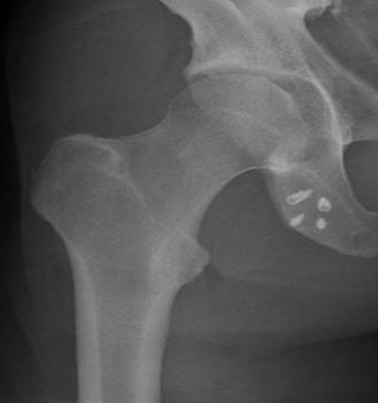

MRI

Peritendinous edema / low grade partial tears / tendinopathy

High grade partial tears